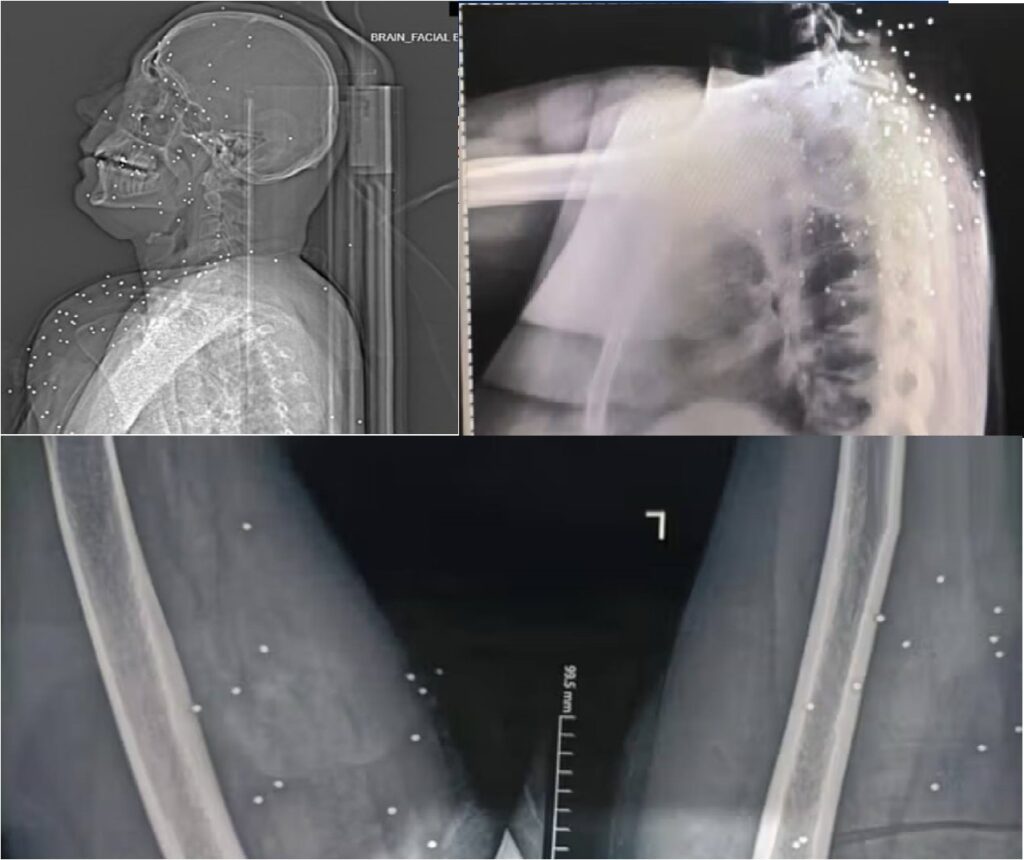

Britaniyanın “The Guardian” qəzeti İranda etirazların yatırılması zamanı təhlükəsizlik qüvvələrinin etirazçıları bədənin həyati əhəmiyyətli nahiylərindən qəsdən hədəfə aldığını açıqlayan araşdırma dərc edib.

Nəşrin məlumatına görə, onlarla tibbi görüntünün təhlili göstərir ki, #etirazçılara qarşı metal mərmilər və yüksək kalibrli güllələrdən istifadə olunub.

Yayımlanan görüntülərdə:

• bir #gəncin boynuna dəyən yüksək kalibrli güllənin traxeyanı sıradan çıxardığı və güclü qanaxmaya səbəb olduğu;

• başqa bir halda güllənin kəllə sümüyünü deşərək beyinə batdığı və ağır beyin zədəsi yaratdığı;

• digər hallarda isə onurğa sütunu və daxili orqanlara yaxın nahiyələrin hədəfə alındığı bildirilir.

Şəkilləri araşdıran ekspertlərdən biri qəzetə açıqlamasında deyib: “Bu cür silahlarla atəş açıldıqda məqsəd öldürməkdir”. Mənbə #yaralılar arasında yeniyetmələr və #uşaqların da olduğunu bildiriblər. (Iranintl)